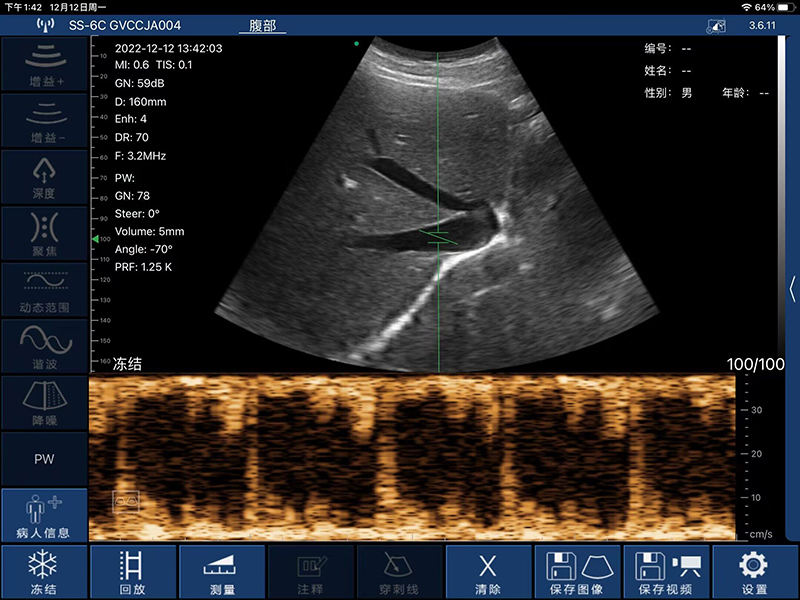

- 探头频率:3.2/5.0MHz

- 扫描深度:90/160/240/305mm,可调

- 显示模式:B、B/M、Color、PW、PDI